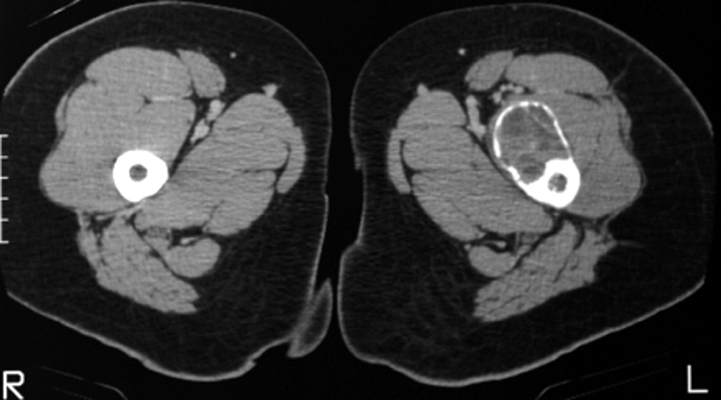

Aneurysmal bone cyst

Frontal radiograph of the right hip and CT scan of the hips on a different patient. Both reveal a cystic bubbly lesion with fine internal septations. Additionally, compromise of the cortical margin of the lesion is present as well. The "blister of bone" sign refers to a bubbly cystic lesion with a saccular protrusion of the cortex with multiple fine internal septae. The shell of the lesion may fracture resulting in extravasation of blood into the adjacent tissues. This sign is highly characteristic of aneurysmal bone cyst.

AP hip - Click on the image for a larger versionA - Click on the image for a larger versionB